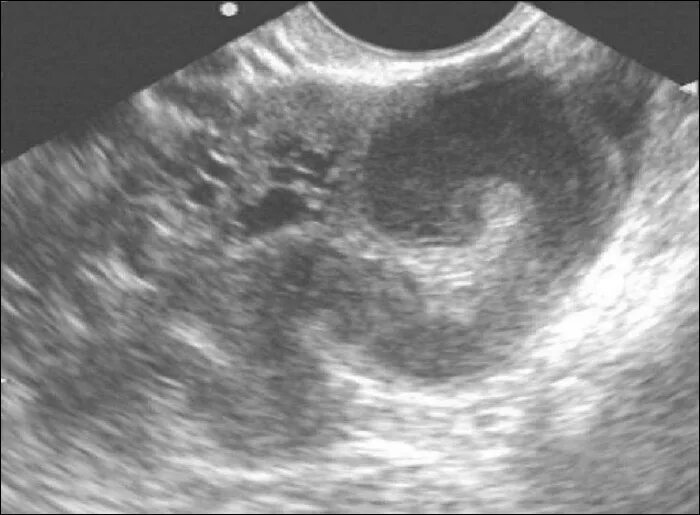

Сальпингит и оофорит что это